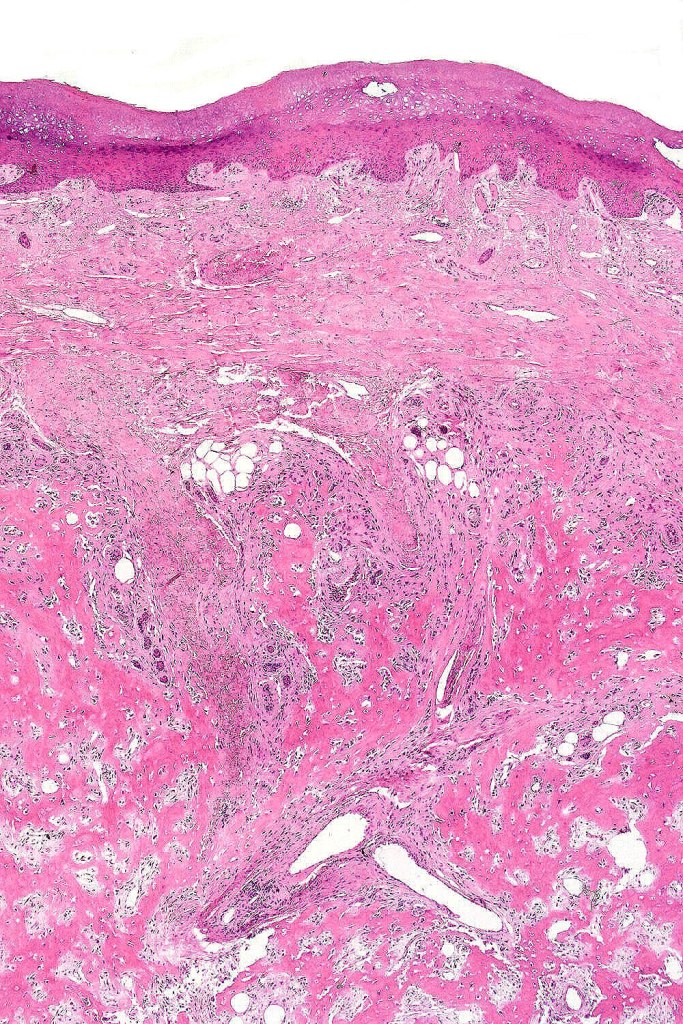

Melanoma with osteoid and chondroid (benign or malignant) are most often encountered in the digits particularly the thumb and large toe, for the other types, they are too rare to make any meaningful clinical comments. Documented heterologous elements include: